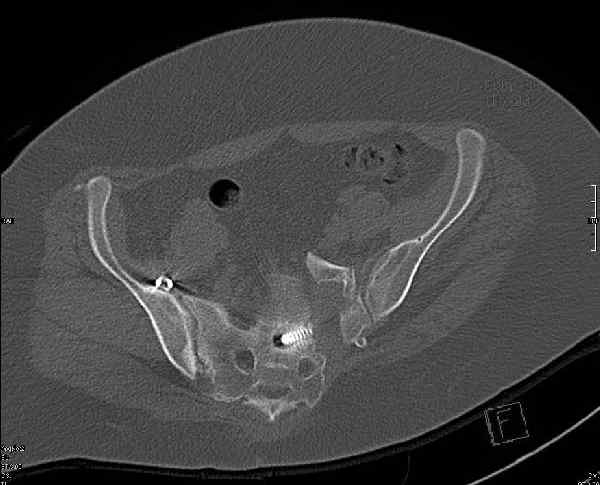

Молодая девушка 19 лет, травма 1 год назад, тогда же прооперирована.

Какова по вашему будет оптимальная тактика в отношении несращения крестца? Замена винтов на более длинные с коррекцией их положения+ туннелизация зоны нестращения, открытое вмешательство с костной аутопластикой или еще какие варианты?

В приложении снимки при поступлении и послеоперационные год назад.

Могу сказать одно: миграция винтов и нестабильность синтеза левого подвздошно-крестцовогоо сочленения очевидна.

Ув.коллега.Думаю, что реостеосинтез винтами бесперспективен.Пороз, наличие большого массива рубцовой ткани, невозможность создать жёсткую фиксацию в зоне ложного сустава крестца требуют изменеия вида остеосинтеза. Тут возможны два варианта.1) Открытый остеосинтез с атупластикой и фиксацией ВЧКО задним стержневым крестцовым аппаратом.2)Тоже самое, но фиксация 2 резьбовыми штифтами типа Штейнемана за заднюю ость подвздошной кости. От выдавливания крестца кпереди следует на этих гвоздяж зафиксировать реконструкционную пластину, которая винтами синтезирует фрагменты крестца.